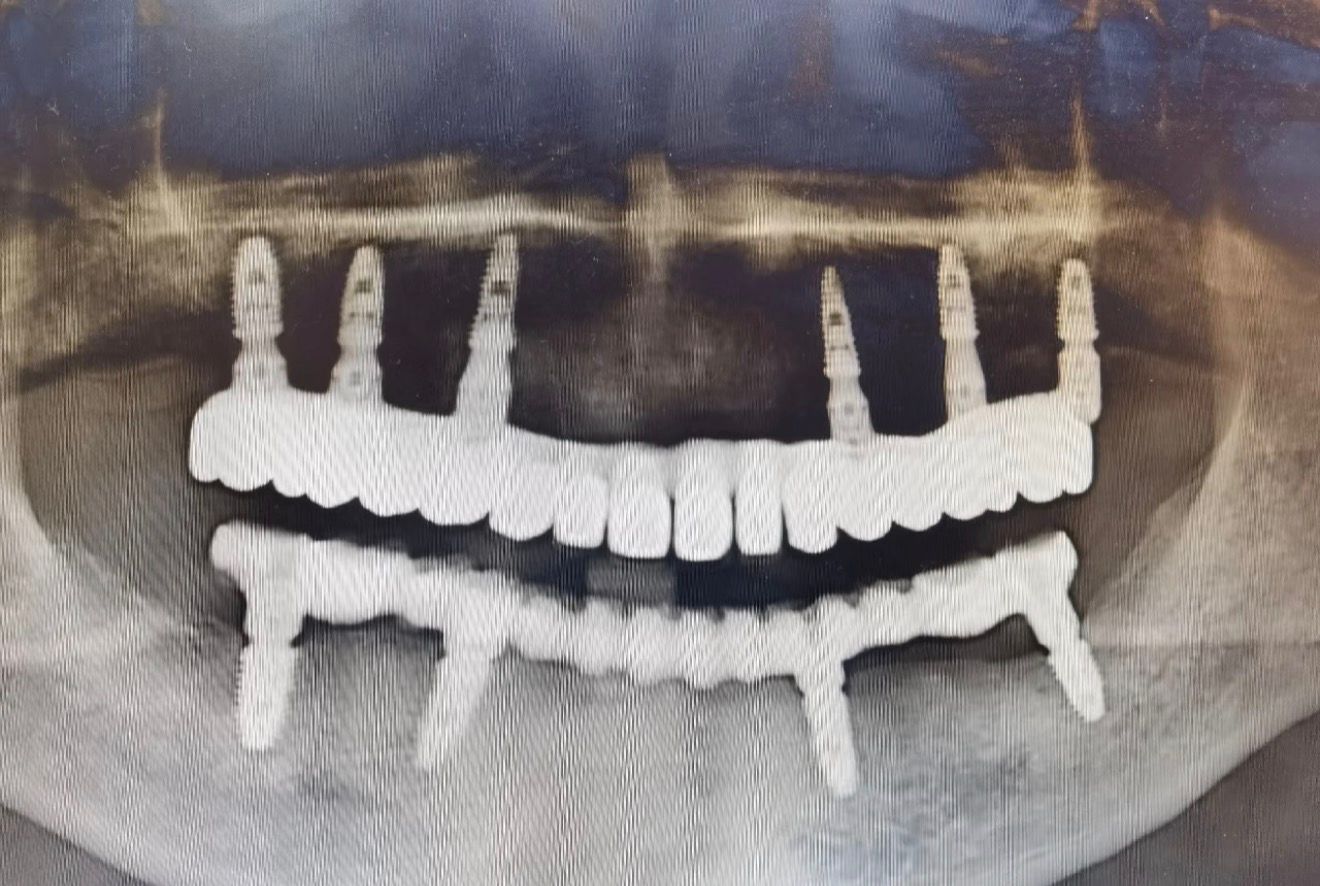

Примеры имплантации зубов в Хуньчуне